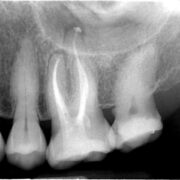

… Wurzelbehandlungen unter dem Mikroskop

Zahntechniker und Zahnarzt. In Leinfelden seit 1999. Überweisungpraxis für mikroskopische Wurzelkanalbehandlungen seit 2002.